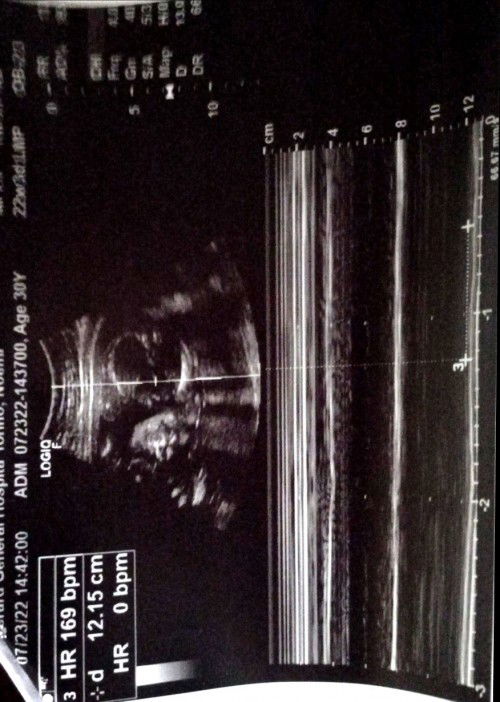

Hello po.... pa help naman po. Ano po kaya yung gender ni baby? Ndi pa po kasi sinabi ng ob/sonologist kasi di pa daw po 100% sure lalo po at naka breech pa si baby. Sana po may makasagot. Thank you in advance po😊